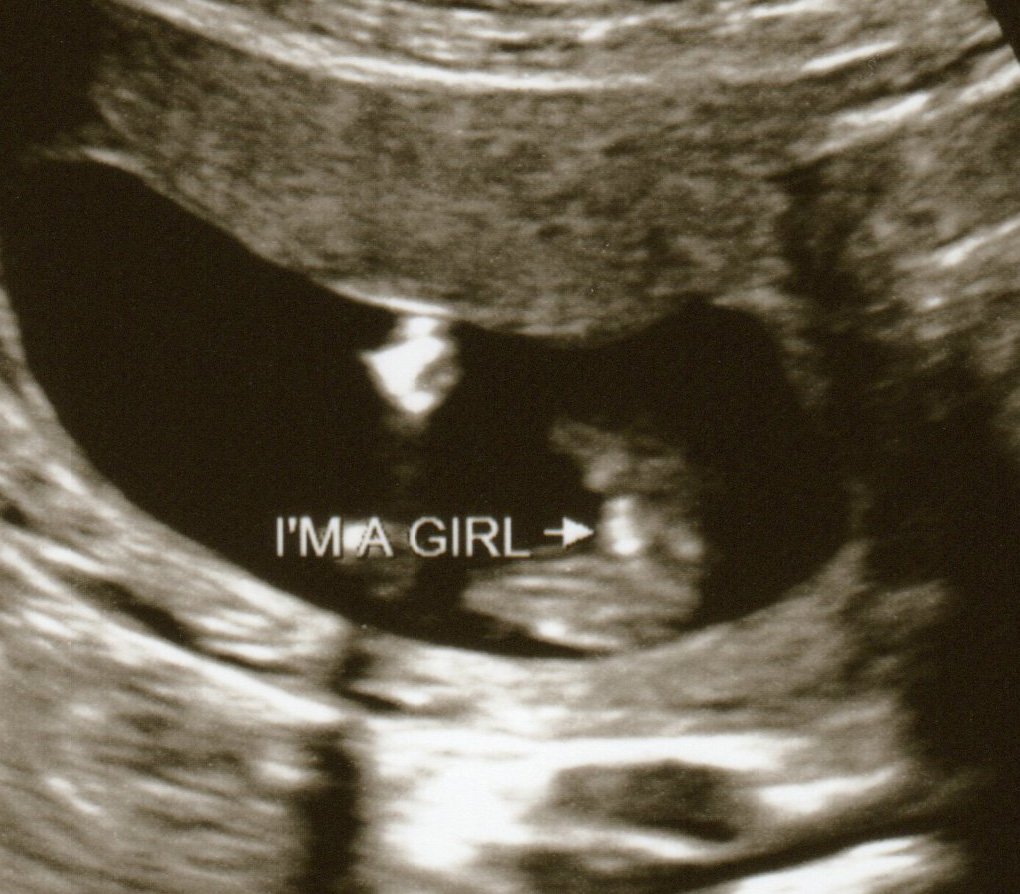

Boy Potty Shot 11 Weeks . This baby is also a boy! This was 13 weeks for us and we are thinking boy from nub shot but i'm pretty sure every baby looks like this so early. The ‘potty shot’ is slang terminology used to describe the moment during an ultrasound when the sex of a baby can be seen. As seen in the image below, 3 dots are visible, indicating penis & testes, bladder is shown (black circle under genitals). Looks like a boy to me :) also a boy mom here and at our ultrasound at around 11 weeks baby did a flip and we got a potty shot. I’ve looked at 100’s of confirmed boy potty shots on the internet and not one looked similar. Both (above and below) images show boy genitals imaging as 3 dots that protrude down the femur. Unfortunately these aren't the potty shots you need at 13weeks. You'll need a clear under view of the butt to get a semi accurate. This is my potty shot at 14 weeks they wouldn’t tell as if it was a boy or girl as to early! The term is commonly used in online. To me it looks too long and dead straight at the sides so is more similar to the cord. Can't look at potty shots that early. We found out at our 20 weeks scan we having a little boy!

This baby is also a boy! Both (above and below) images show boy genitals imaging as 3 dots that protrude down the femur. The term is commonly used in online. The ‘potty shot’ is slang terminology used to describe the moment during an ultrasound when the sex of a baby can be seen. This is my potty shot at 14 weeks they wouldn’t tell as if it was a boy or girl as to early! Can't look at potty shots that early. This was 13 weeks for us and we are thinking boy from nub shot but i'm pretty sure every baby looks like this so early. We found out at our 20 weeks scan we having a little boy! Looks like a boy to me :) also a boy mom here and at our ultrasound at around 11 weeks baby did a flip and we got a potty shot. You'll need a clear under view of the butt to get a semi accurate.

Boy Potty Shot 11 Weeks We found out at our 20 weeks scan we having a little boy! I’ve looked at 100’s of confirmed boy potty shots on the internet and not one looked similar. We found out at our 20 weeks scan we having a little boy! This is my potty shot at 14 weeks they wouldn’t tell as if it was a boy or girl as to early! You'll need a clear under view of the butt to get a semi accurate. Looks like a boy to me :) also a boy mom here and at our ultrasound at around 11 weeks baby did a flip and we got a potty shot. Both (above and below) images show boy genitals imaging as 3 dots that protrude down the femur. This was 13 weeks for us and we are thinking boy from nub shot but i'm pretty sure every baby looks like this so early. The term is commonly used in online. As seen in the image below, 3 dots are visible, indicating penis & testes, bladder is shown (black circle under genitals). Unfortunately these aren't the potty shots you need at 13weeks. The ‘potty shot’ is slang terminology used to describe the moment during an ultrasound when the sex of a baby can be seen. To me it looks too long and dead straight at the sides so is more similar to the cord. Can't look at potty shots that early. This baby is also a boy!